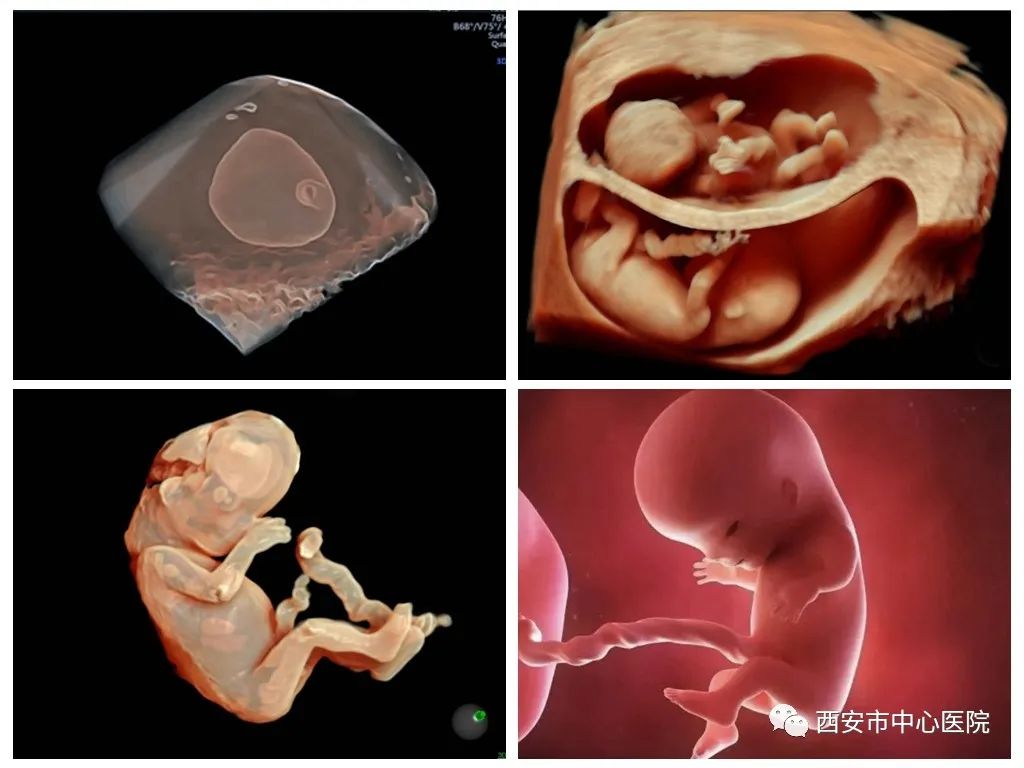

怀孕之后宝妈们要做一系列的产检来检测胎儿的健康。其中,超声检查是至关重要的辅助检查,它可以了解孕期胎儿的变化和生长状况,每个宝妈都已经非常熟悉孕中期要做系统超声、四维超声(22-26孕周)及胎儿心脏检查(22-28W),进行全方位的胎儿排畸筛查。随着超声仪器的进步和医生操作技术的提高,更重要的是为了重视母婴健康和人文关怀,提倡将胎儿畸形筛查时间提前,尽早筛出异常胎儿,尤其是有严重畸形的胎儿,尽可能减轻引产导致的孕妇心理及生理创伤。

卫生部规定的中孕超声应筛出的6大畸形:无脑儿、严重脑膨出、严重的开放性脊柱裂、严重的胸腹壁缺损伴内脏外翻、单腔心、致死性软骨发育不良,是严重影响胎儿健康的畸形,除了致死性软骨发育不良和部分脊柱裂往往发现较晚外,大部分都能在孕早期系统筛查中得到确诊,无须再拖到20周以后。

胎儿主要器官在孕12周前已基本形成,超过80%的畸形在此阶段已经形成,故孕11~19+6周是超声筛查胎儿结构异常的重要时期,可检出40%~70%的严重先天性畸形,除了上述的5种重大畸形外,如对无叶全前脑、淋巴水囊瘤、脐膨出、心脏异位、巨膀胱、手足缺失、鼻骨缺失、肢体缺失、单心室、完全性心内膜垫缺损、三尖瓣重度返流等,均能做到出色的检查效果,可以做到早发现、早诊断、早决策。

检查时间:11孕周后皆可进行,孕13-18W最佳(有特殊需要者可放宽至孕20W)。因为胎儿发育是一个动态的不断变化的进程,即使早期系统筛查无异常,也必须在中孕期做相关的详细超声检查,不能替代。

本科室目前采用国际一流的高端四维产科超声仪VOLUSON E8/E10进行早期系统筛查,功能强大,图像高清,分辨率高,在孕11-14周就检出过单心室、心内膜垫缺损、肢体缺失、脊柱裂、鼻骨缺失、18三体、21三体、特纳氏综合征等多种异常。